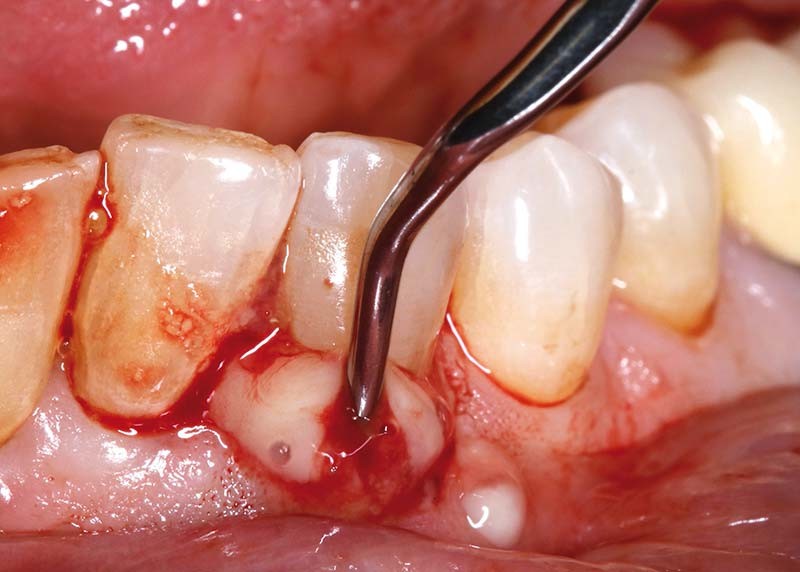

Cliniquement, la gencive présente un aspect tuméfié, rouge/violacé ; elle est lisse, brillante et à tendance hémorragique (fig. 1). Une suppuration, majoritairement par le sulcus, est observée de manière spontanée ou provoquée sous légère pression. La palpation et la percussion sont douloureuses. Une mobilité dentaire, variable selon l’atteinte desmodontale, peut être présente.

– par la poche parodontale par débridement (insert U.S et/ou curette de Gracey) (fig. 3),